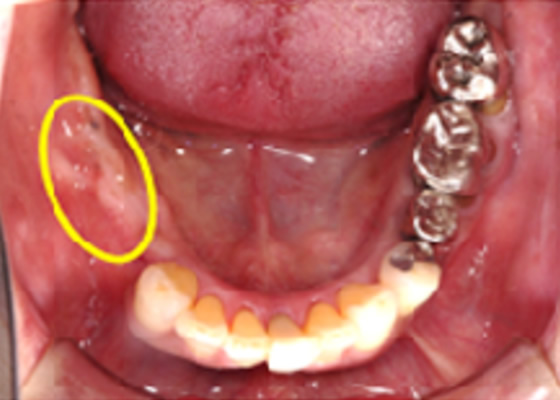

治療内容:奥歯が噛めない、歯を白くしたいという主訴に対して、インプラント治療、セラミック治療を行った症例。

治療費:¥220,000~/1本×2 ハイブリッド冠¥55,000×2 診断料:¥22,000

副作用・リスク:インプラントオペによる一時的な炎症・出血や顔面の内出血、治療終了後のメンテナンス不足による歯周病やインププラント周囲炎、歯ぎしりや過剰な噛み締めによるセラミックスの破折。